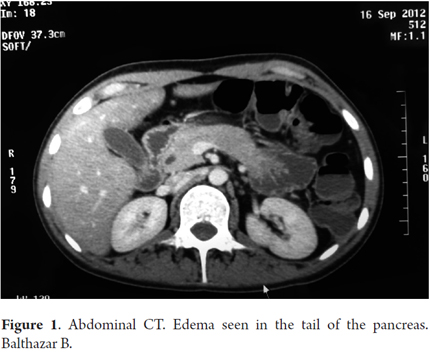

A thoracoabdominal-pelvic CT scan also showed an enlarged pancreas plus a dilated Wirsung's duct (see Figure 1). In accordance with the clinical and radiological evidence the patient was diagnosed with acute pancreatitis. Magnetic resonance cholangiopancreatography (MRCP) confirmed the previous findings. Additional tests had the following results. A toxoplasma and a cytomegalovirus blood test were both negative for IgM while the toxoplasma test was also negative for IgG, but the cytomegalovirus test was positive for IgG. A herpes 1 blood test was negative for IgM, but positive for IgG. A herpes 2 blood test was negative for both IgM and IgG. To evaluate the presence of cytomegalovirus, a real-time polymerase chain reaction (RT-PCR) was also requested. It detected 2887 copies/mL. Administration of ganciclovir was initiated immediately and continued for 12 days leading to a remarkable clinical recovery.